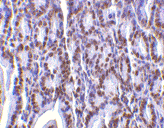

Below: Immunohistochemistry of PHAP I in mouse small intestine tissue with PHAP I antibody at 2 µg/ml.